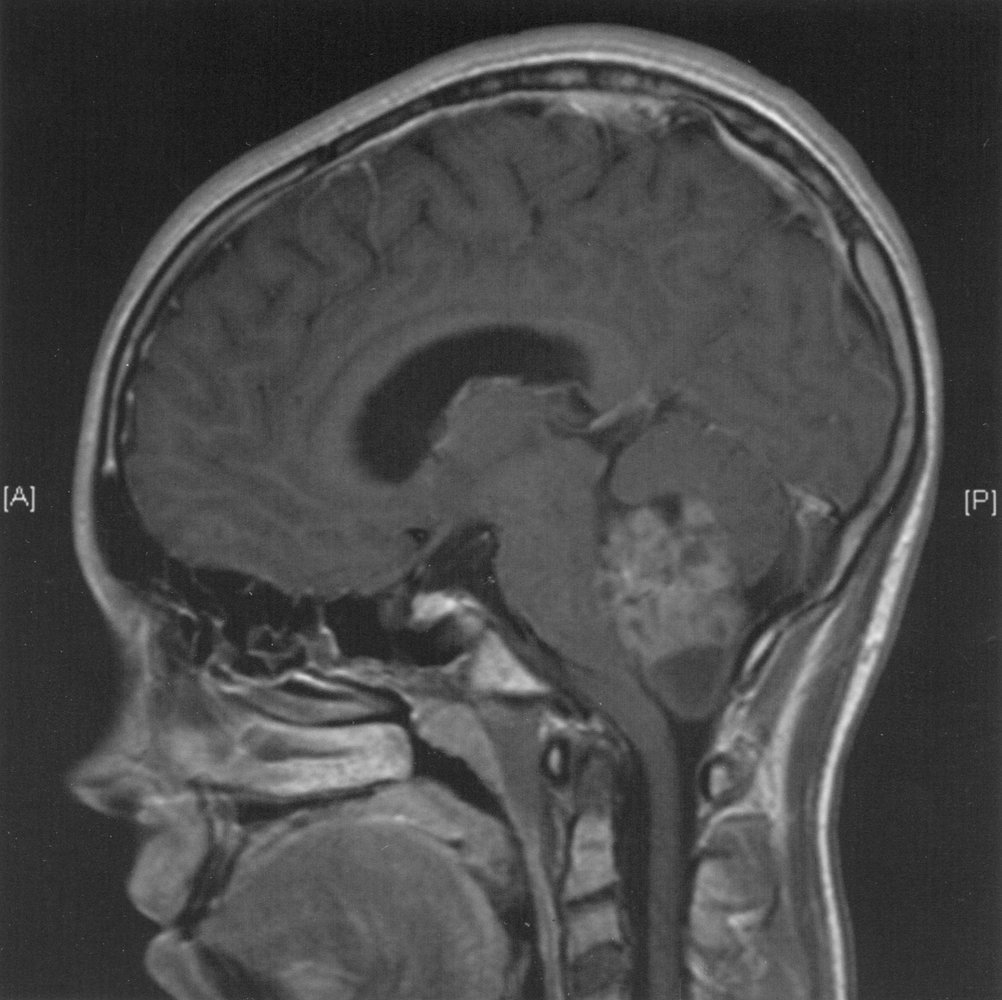

Typical locations of various brain tumors

Most common cause of acquired hypopituitarism in children

Craniopharyngioma